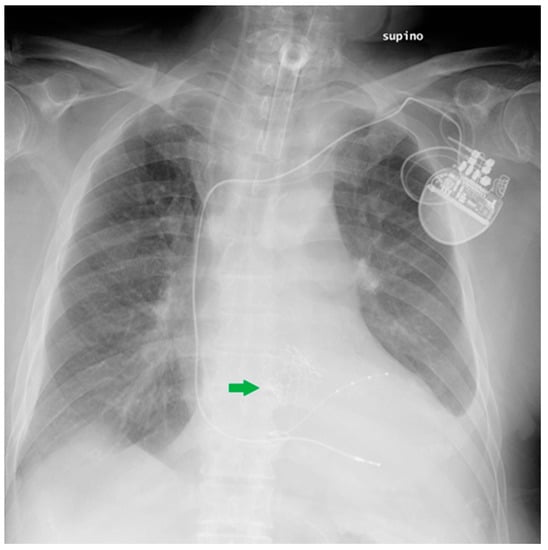

5.2. Pacemaker (PM) and Automatic Implantable Cardioverter-Defibrillator (AICD)

5.3. Ventricular Assistance Devices (VADs)